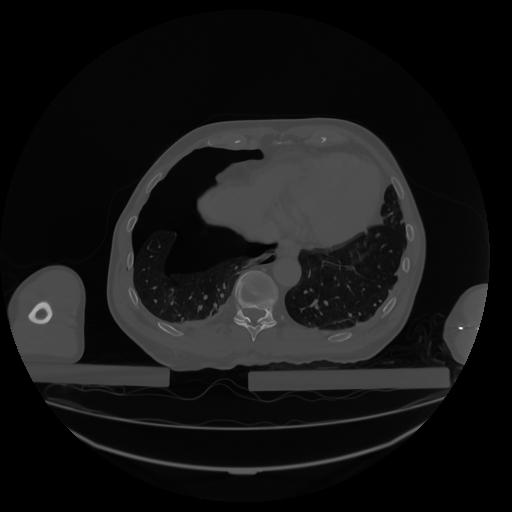

34 CUERPO,CE,Vol,1.0,CUERPO,,